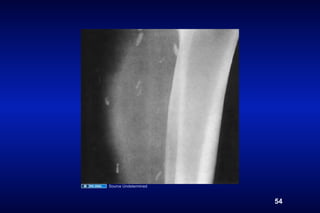

Source Undetermined

54

• 54.

Taeniasis poor sanitation ingestion of undercooked pork poor hygiene Tapeworm Cysticercosis (pig) Martin von Nathusius, wikimedia commons 53 Cary Engleberg (All other images)